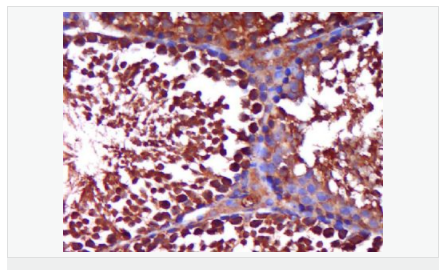

AR是一個(gè)由917個(gè)氨基酸組成的蛋白質(zhì),位于雄激素靶組織細(xì)胞中或細(xì)胞表面上的特異分子部位或結(jié)構(gòu)。 AR在前列腺癌中起著重要的作用,研究表明AR的表達(dá)與組織分型形成一定的相關(guān)性 ,AR在高分化的腫瘤中表達(dá)較多,而在低分化的腫瘤中表達(dá)較少。用于前列腺癌的檢測(cè),指導(dǎo)臨床治療,目前可用于乳腺癌、食道癌等各項(xiàng)腫瘤的研究。

image.png